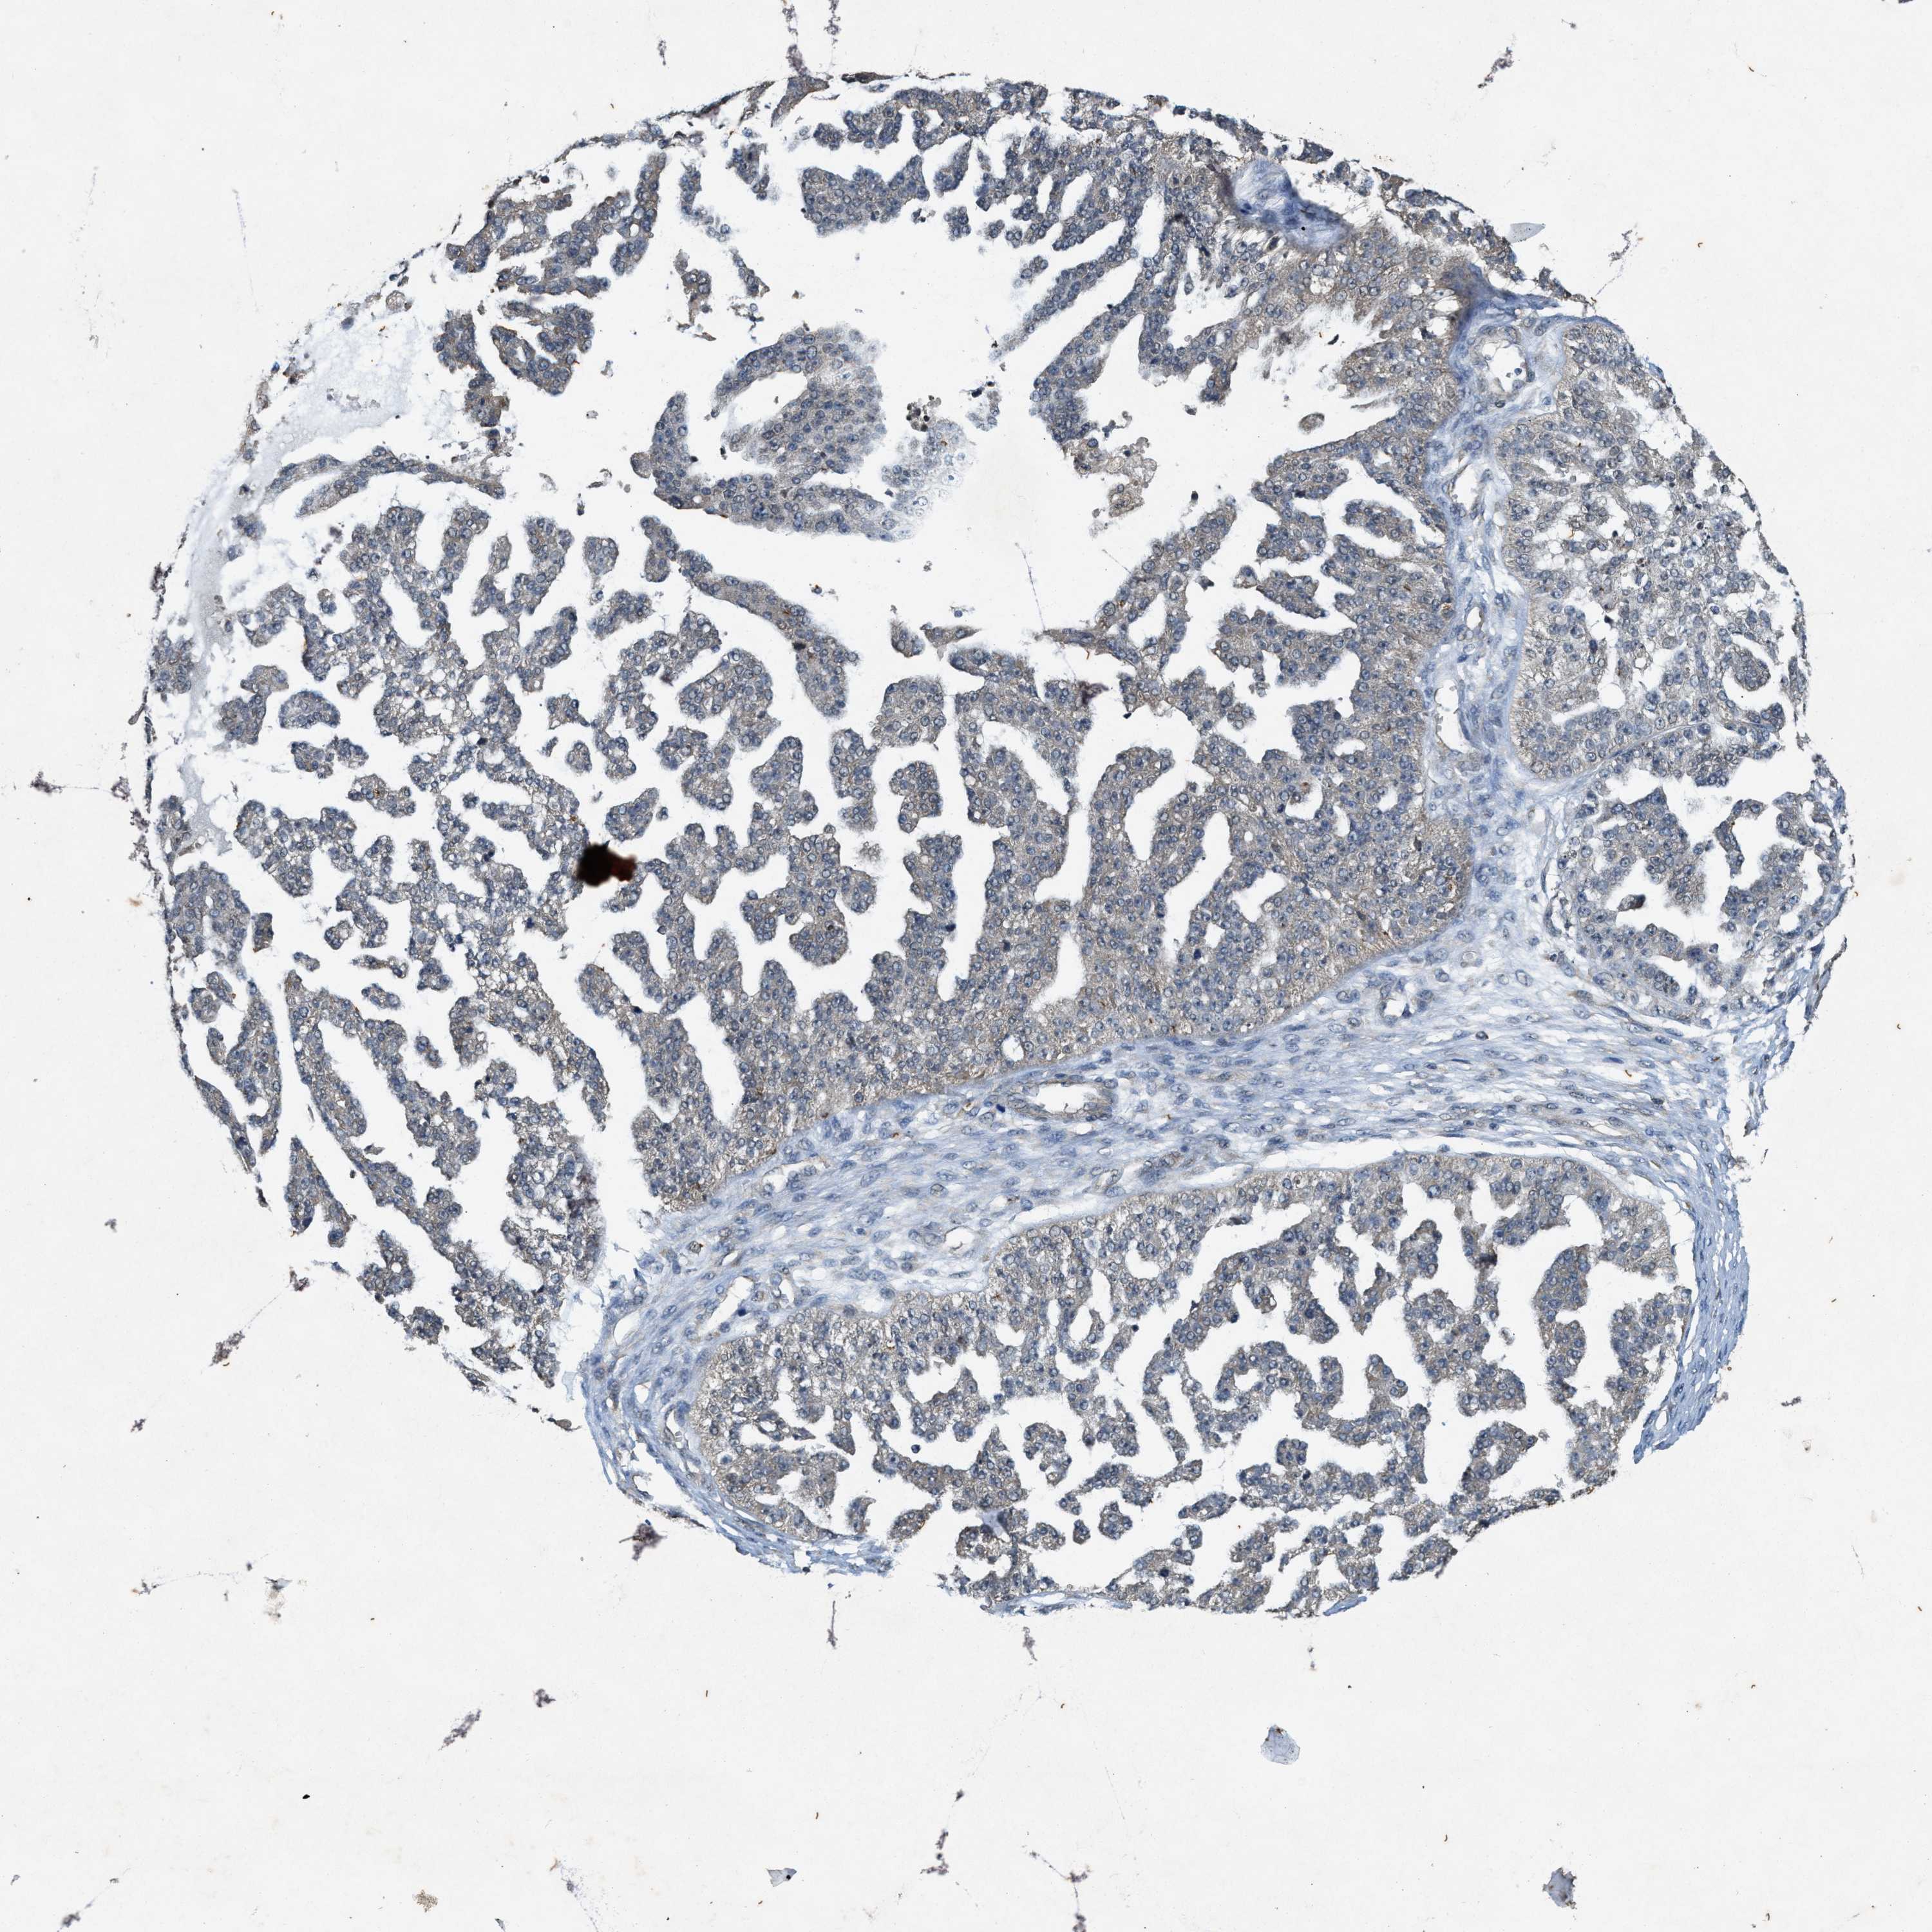

OVARIAN CANCER - Protein expressioni

A mouse-over function shows sample information and annotation data. Click on an image to view it in a full screen mode. Samples can be filtered based on level of antibody staining by selecting one or several of the following categories: high, medium, low and not detected. The assay and annotation is described here.

Note that samples used for immunohistochemistry by the Human Protein Atlas do not correspond to samples in the TCGA dataset.

Antibody stainingi

Antibody staining in the annotated cell types in the current human tissue is reported as not detected, low, medium, or high, based on conventional immunohistochemistry profiling in selected tissues. This score is based on the combination of the staining intensity and fraction of stained cells.

Each image is clickable and will lead to virtual microscopy that enables deeper exploration of all samples and also displays staining intensity scores, fraction scores and subcellular localization as well as patient and tissue information for each sample.

Antibody HPA058432

Antibody CAB022079

Cystadenocarcinoma, mucinous, NOS